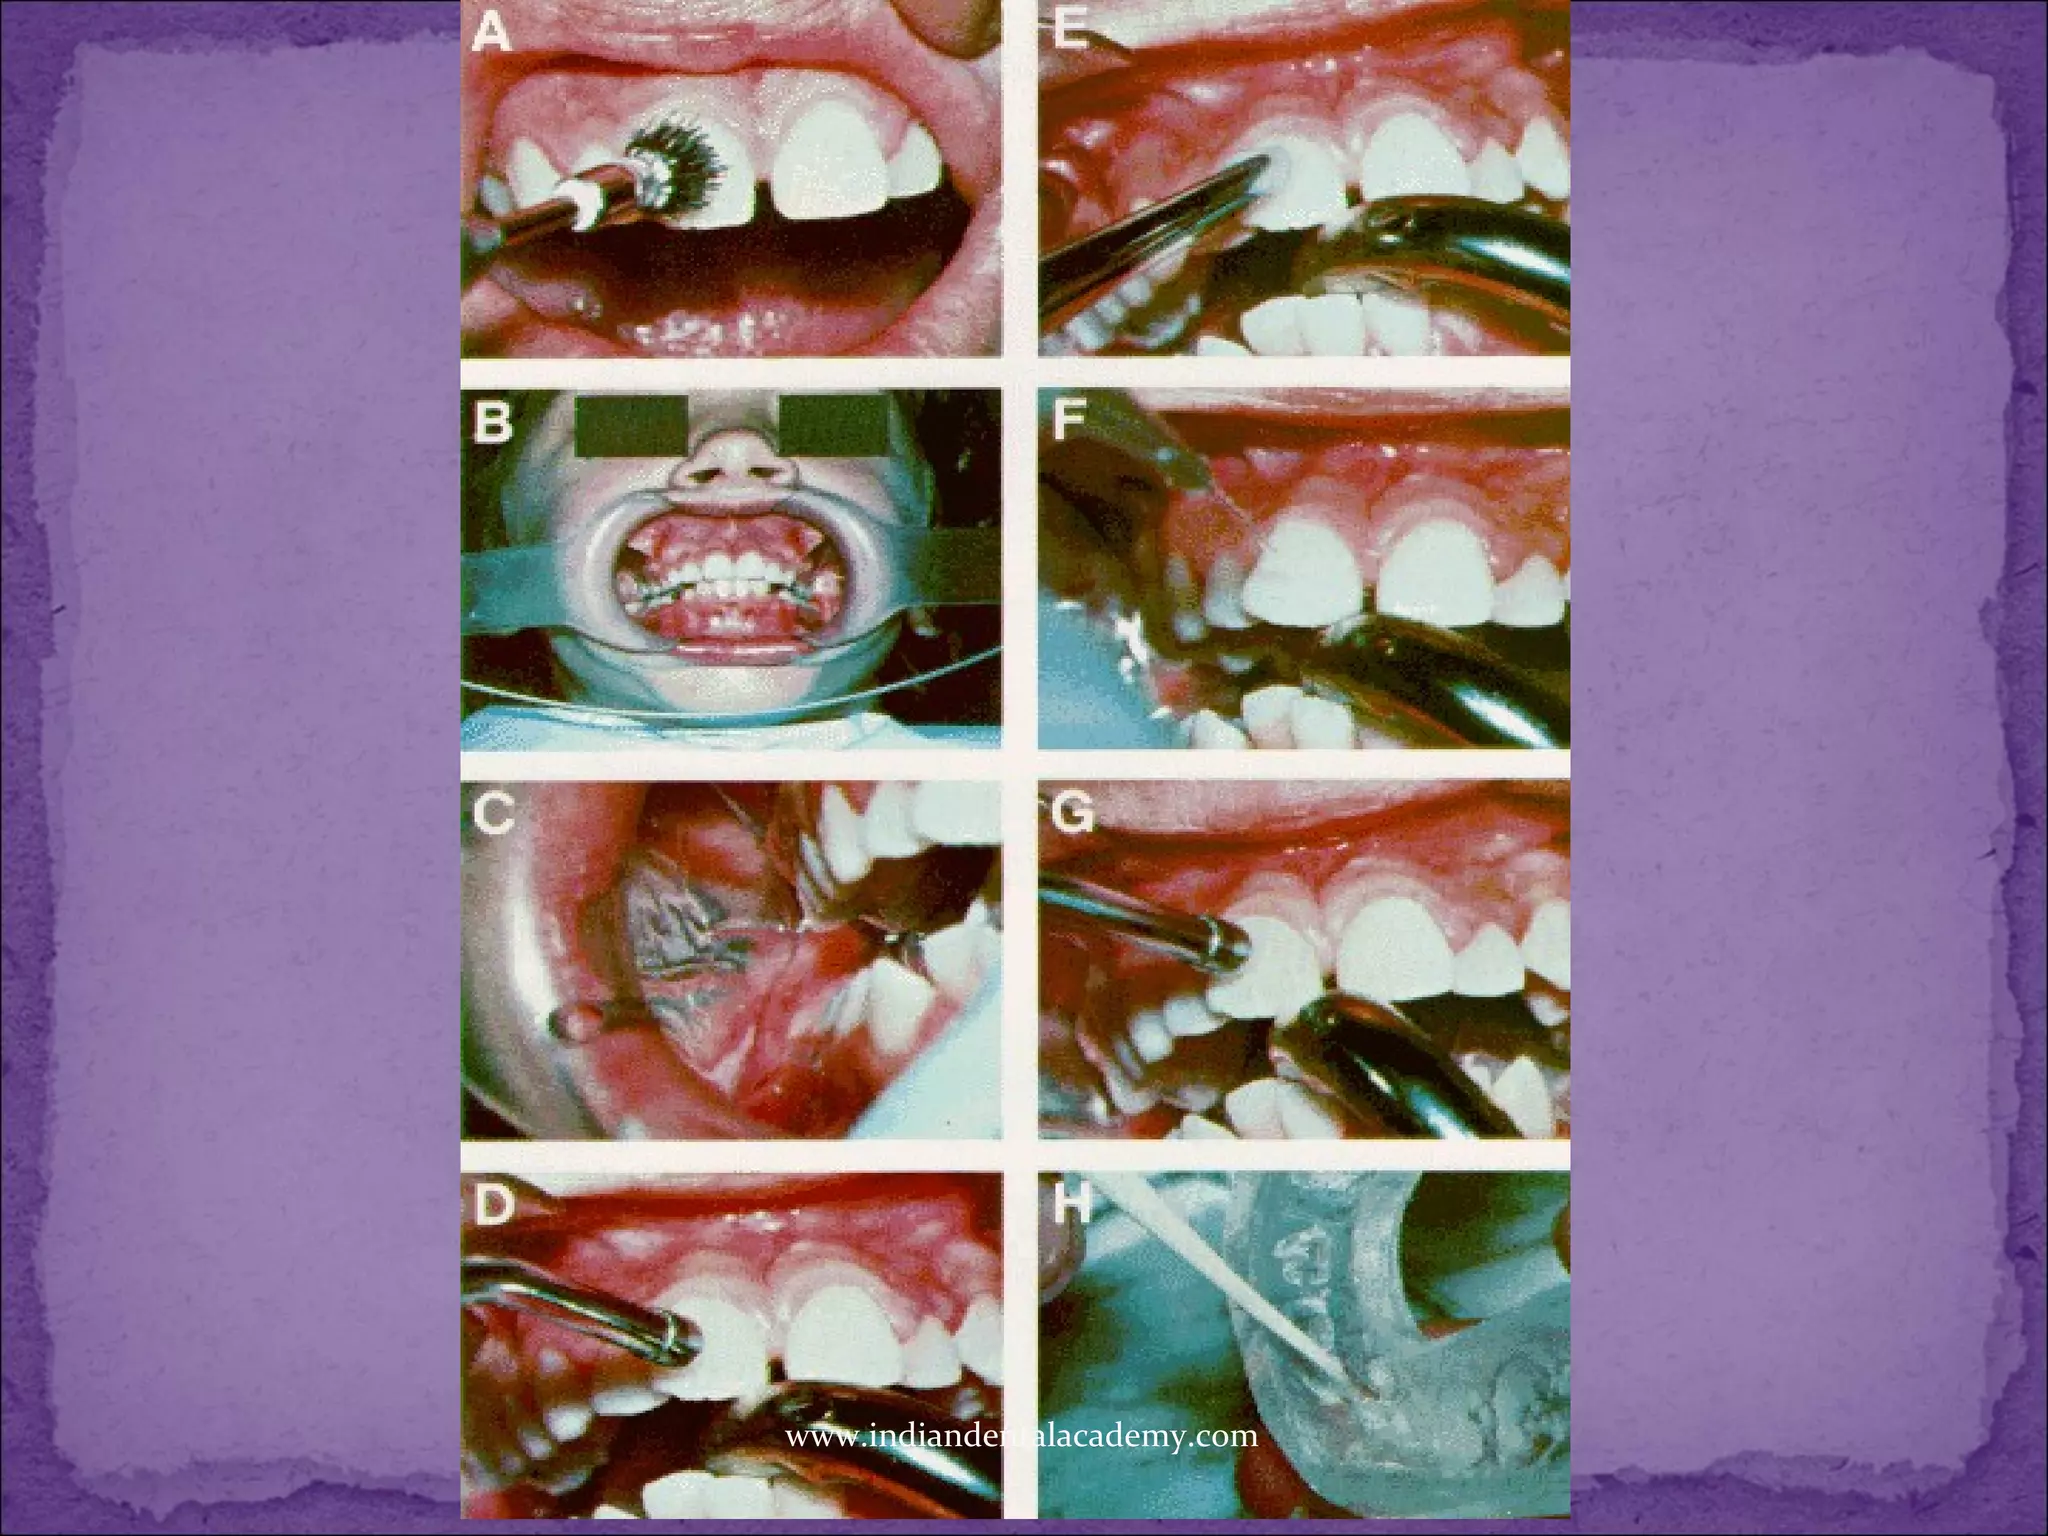

Nuva-Tach facing on the model

First we take impressions of the teeth and make two

sets of models.

Lab man then puts a separating medium on the stone

teeth of the work model.

 Next, cover almost the entire labial and buccal

surfaces of the teeth short of the contact points and

the gingiva with a layer of Nuva-Tach which forms a

backing for the attachments and a facing for the

teeth.

Placing the brackets on the model

After the Nuva-Tach has been shaped to the desired

backing or facing on the model teeth, brackets are placed

in their desired positions on each of the teeth, with their

flanges covered.

Curing the facings on the model

When all the attachments have been placed, the individual

teeth on the model are treated with the ultraviolet light to

cure the Nuva-Tach.

Once the Nuva-Tach on the model teeth has been

polymerized, a plastic wafer is vacuum-molded over the

teeth, facings and attachments. The material use is about

1/16" thick

Vacuum-formed plastic tray

When the vacuum-formed plastic wafer is removed

from the work model, it takes the attachments and

the hardened Nuva-Tach facings with it.

The wafer is then trimmed.

Now we have a plastic tray ready to be placed in the

mouth

But first we have to prepare the teeth.

Tooth surface preparation

The first step in preparing the tooth surface is

pumicing followed by acid conditioning.

Polymerizing the Nuva-Seal coating

The Nuva-Seal is then painted on the tooth surfaces and

polymerized with the ultraviolet light.

Seating the tray

With the thin layer of fresh Nuva-Tach applied to the

backings to be bonded, the tray is placed directly in the

mouth and forced onto the teeth, both sides at the same

time. However, generally bond only one side at a time.

the tray is seated completely, the brackets and facings are

exposed to the ultraviolet light for 90 seconds per tooth

through the tray.

Removing the tray

When the tray is removed, the bonded brackets remain on

the teeth and the unbonded ones remain in the tray. The

inside of the tray is now washed and dried

thoroughlyThen we bond the second side in the same

manner as the first